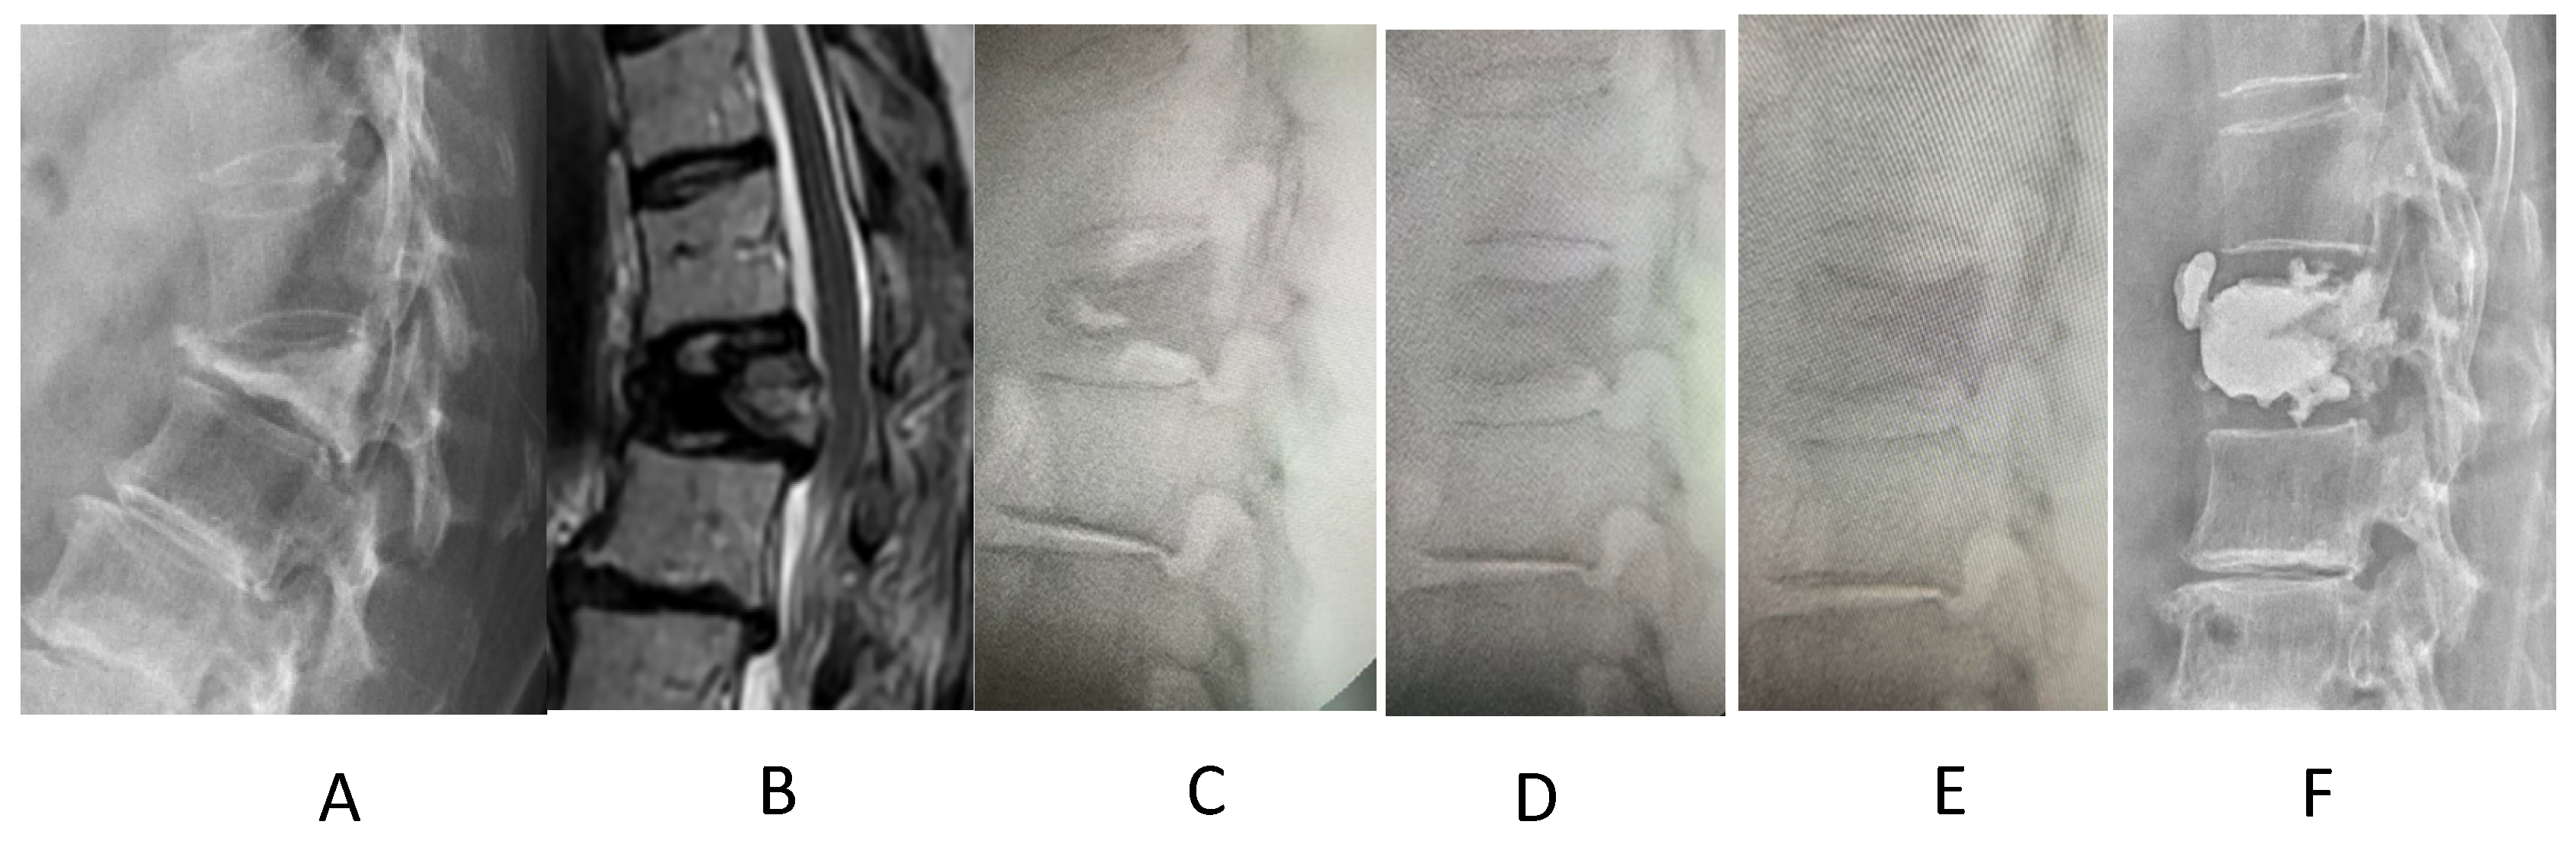

Manual Reduction for Subacute Osteoporotic Burst and Severe Compression Thoracolumbar Fractures

2. Materials and Methods

3. Results